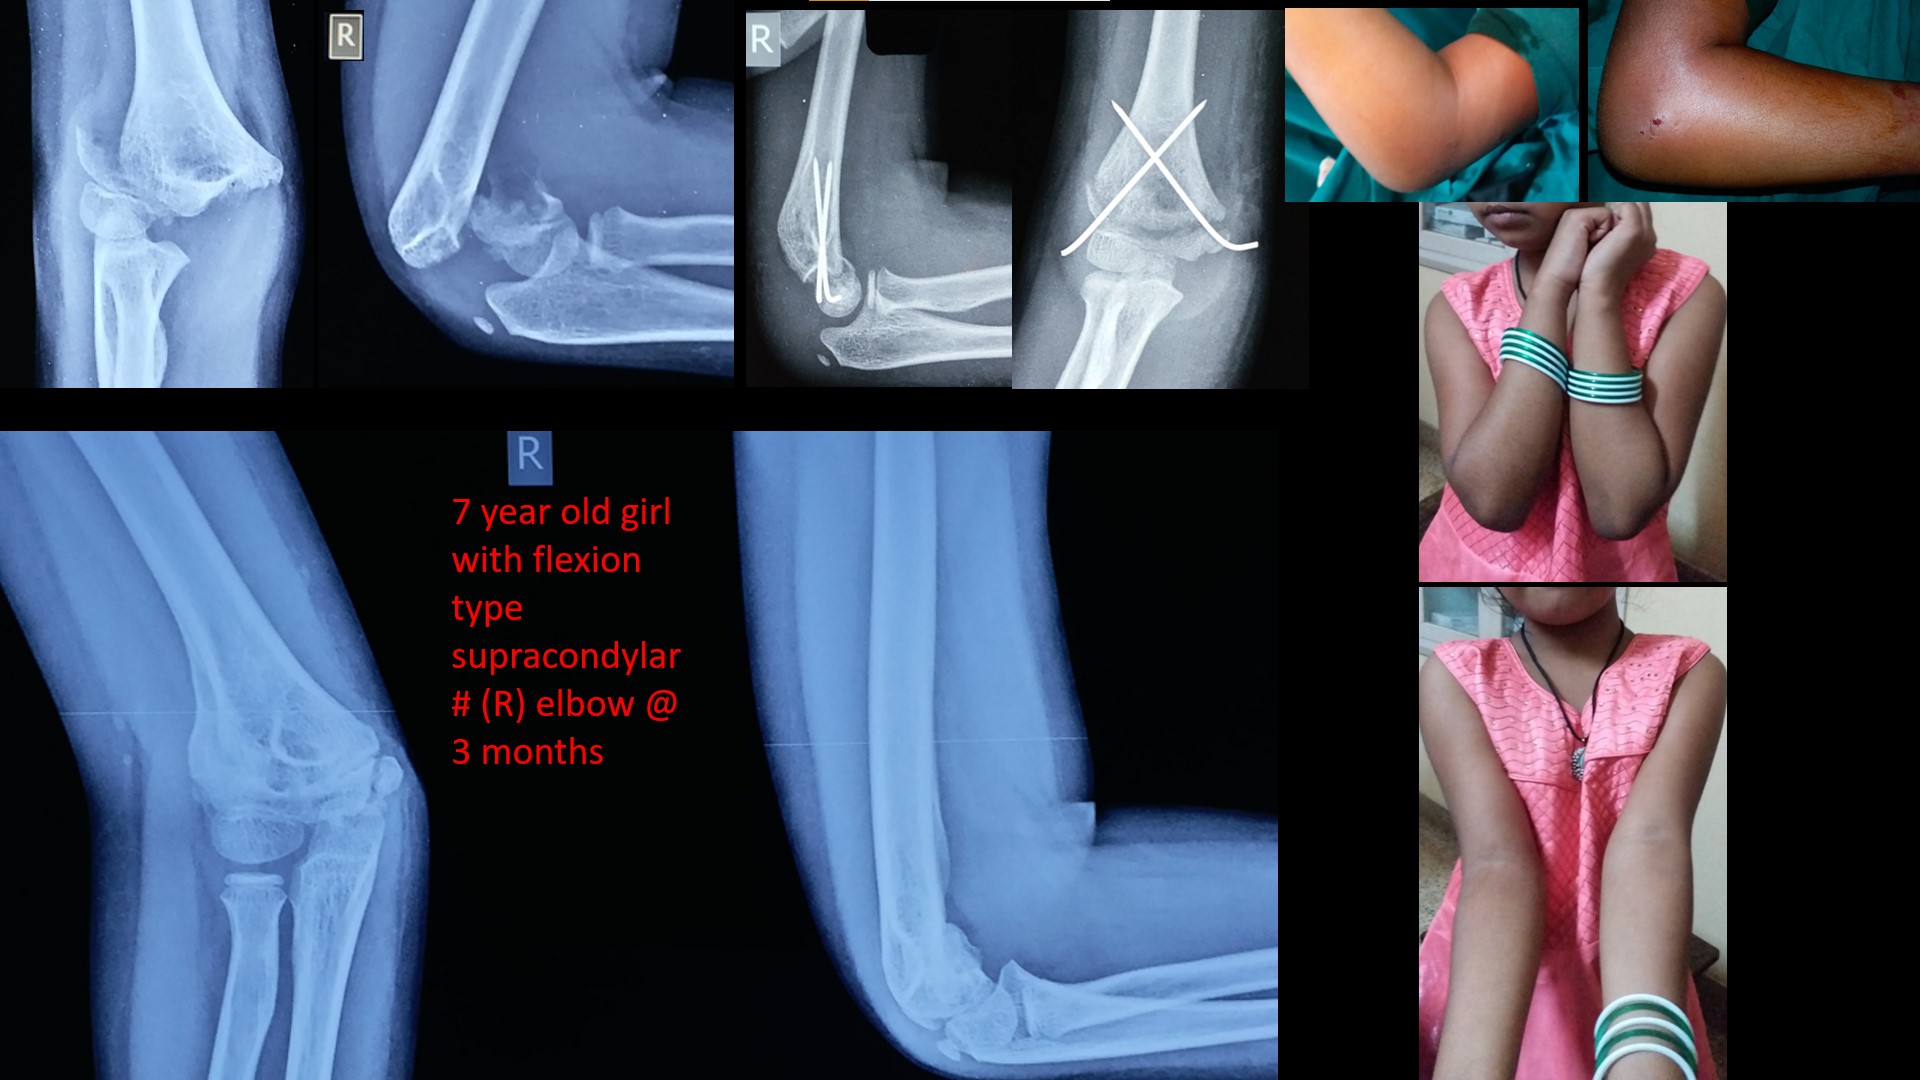

SUPRACONDYLAR #